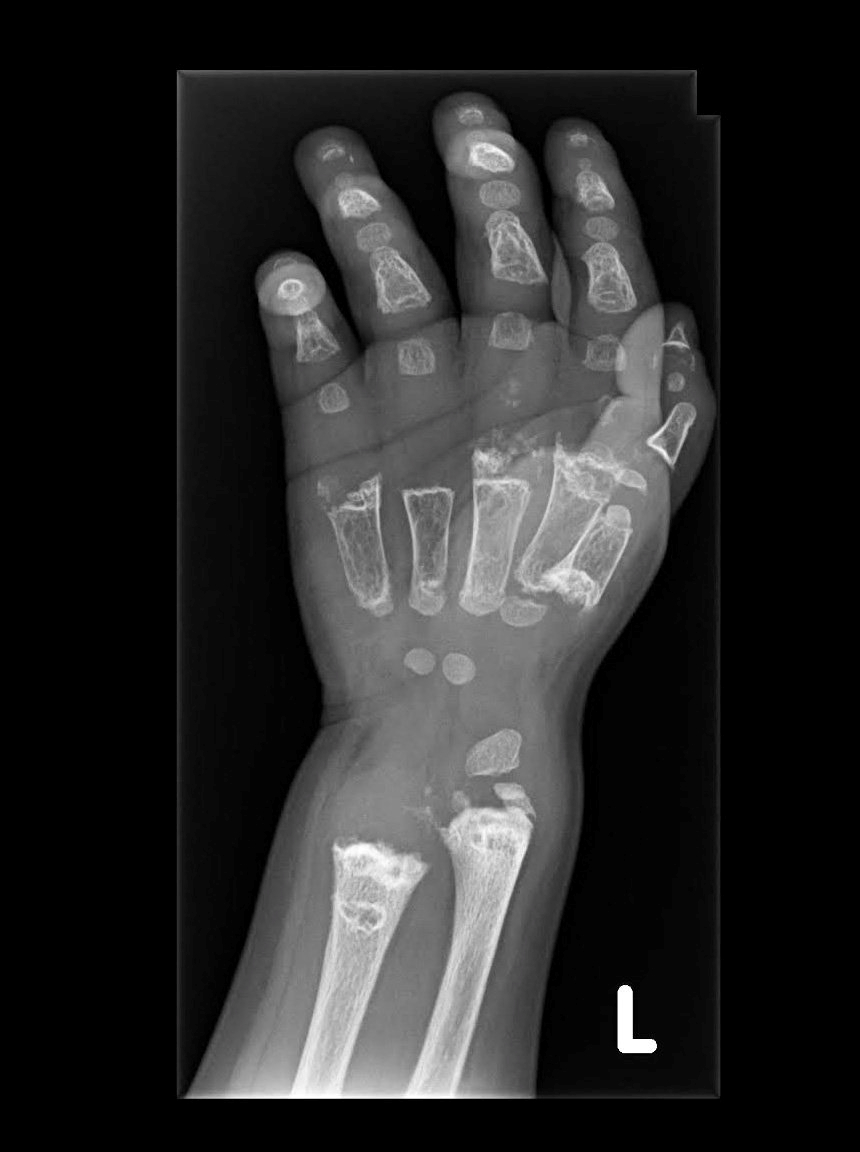

Neena and her two sons are three of the fewer than 30 people around the globe who have been diagnosed with Jansen’s, which is caused by a genetic mutation. Though not terminal, the diagnosis means chronic pain and dozens of corrective surgeries to straighten weak bones that grow in serpentine curves, fraying at the ends like old paintbrushes. The disease also can lead to kidney problems, caused by the high levels of calcium in the bloodstream.

For the two Elkhorn boys with the wide brown eyes, quick smiles and an obsession with superheroes, the diagnosis means always being the smallest one in their classrooms and not being able to join friends at recess for games of basketball. It means every vacation is planned around a surgery or a doctor’s visit. It means being unable to take medication for the pain, for fear that it would further stress their kidneys. The surgeries likely will stop once the boys stop growing, but even then, their bones will be so weak they may not be able to walk.

But the reminders are there: the leg braces, the wheelchairs, the long dark scars running up and down their legs from the several surgeries and the metal fixation rings once drilled into their tibias.